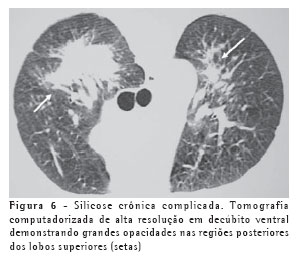

Os achados iniciais na TCAR consistem em micronódulos centrolobulares e subpleurais (Figura 4), menores que 0,5 cm. Com a evolução da doença estes micronódulos tendem à confluência, com formação de nódulos maiores (Figura 5), conglomerados (Figura 6) e, numa fase mais tardia, massas fibróticas, geralmente com calcificações e aumento irregular do espaço aéreo adjacente (Figura 7).(5)